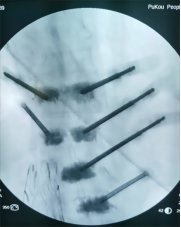

7. 复杂脊柱骨折内固定技术

随着区域内社会经济开发,复杂严重脊柱脊髓损伤病例增加,如何良好的手术治疗解除脊髓压迫、重建脊柱稳定性,使患者创伤最小、收益最大是促进患者康复至关重要的一环。皇冠娱乐城

已熟练开展各类脊柱损伤修复重建技术,每年完成复杂脊柱骨折手术处于区域领先水平。